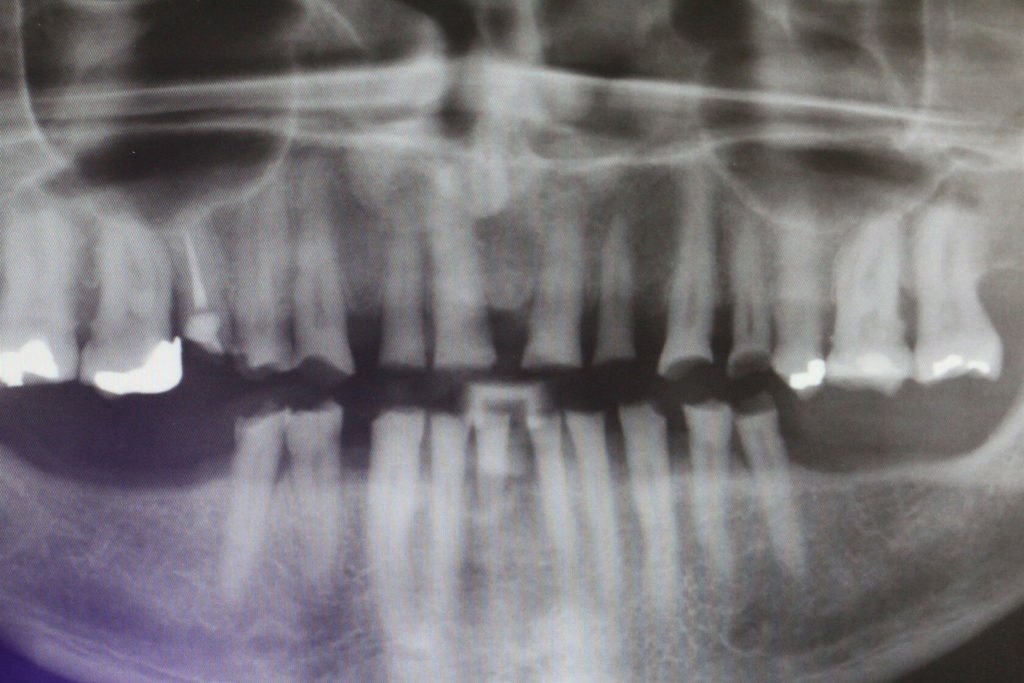

This 50 year old patient was in today for a check-up on his teeth. I had not seen him for 20 months since we restored his lower teeth. We had restored his upper teeth 2 months previous to doing his lower teeth. He came from another neighboring dental office where they don’t do composite rehabs. He has been into this other office for several cleanings since we did his rehab but he smokes, loves his coffee and has lots of stain. Anyway I was wondering how he was making out with his new teeth and he was very satisfied. In his words “no pain or sensitivity or problems”. So I was quite happy with his rehab. His wife came as well and we knew each other from 30 years ago when my daughters and I were riding horses in the same horse club. There were a few air bubbles that I didn’t like and a small open margin that I repaired and that was all he needed to spiffy him up.